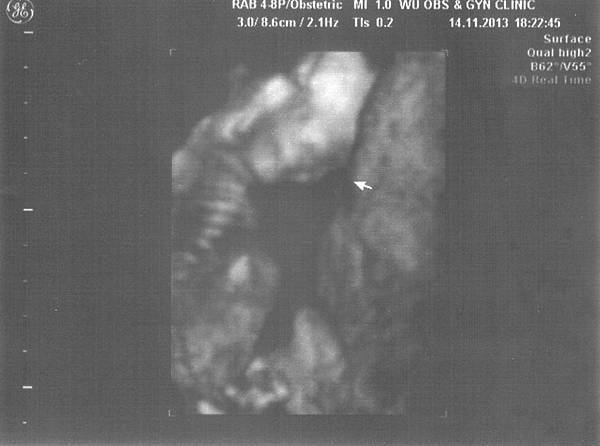

按慣例,當然還是要照個超音波來跟小小寶貝打招呼~

聽說箭頭指的是小GG

但因為只有一咪咪,但我想應該也八九不離十了!

照超音波過程,小小寶貝也是相當忙碌,

一直在跑步,不知道是不是想學馬陰囧呢XD